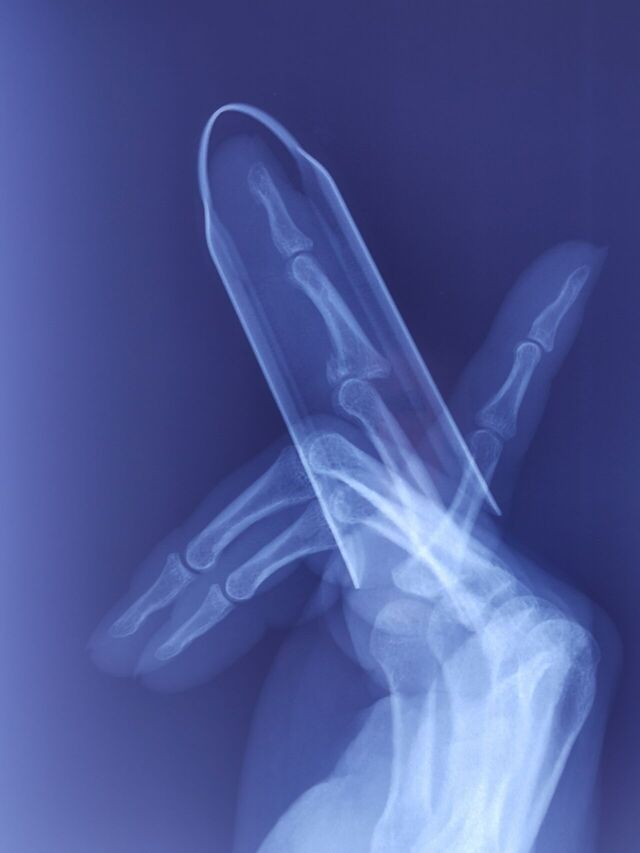

杭州整形医院姚建民教授分享的病例

微信截图_20240202162039.png

微信图片_20240202162058.jpg

微信图片_20240202162101.jpg

同一个病人,不同的手指,相同的方法